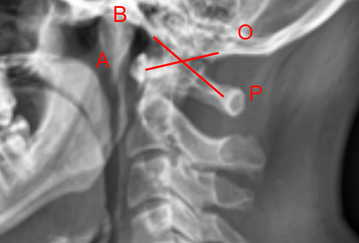

Image Type Cervical Spine X-Ray CT Scan MRI Scan Atlantodental Interval (ADI) Basion-Axial Interval Basion-Dens Interval (BDI) C2 Tilt C2–C7 Coronal Cobb Angle Cervical C2-7 lordosis C2-C7 Translation Chamberlain’s Line / McGregor’s Line Flexion-Extension George’s Line (Posterior Cervical Line) K-Line Interpedicular Distance (IPD) Occiput-C2 Angle Occipital Condyle–C1 Interval (CCI) Posterior Atlantodental Interval (PADI) Power’s ratio Sagittal Canal Diameter Sagittal Vertical Axis (SVA) Spinolaminar line Swischuk Line T1 Slope Torg/Pavlov Canal-to-Body Ratio